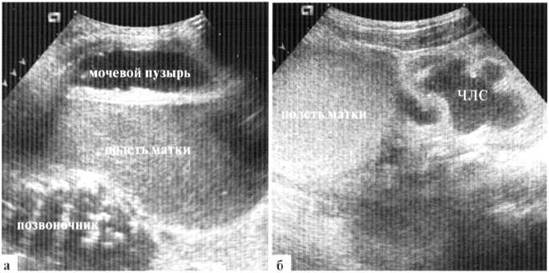

Гидрометрокольпос у новорожденных встречается редко, клинически проявления в виде «синдрома пальпируемой опухоли» в животе, иногда видна неперфорированная плева, выступающая между малыми половыми губами. При УЗИ определяется относительно толстостенное, округлой формы образование в животе, содержимое его обычное мелкодисперсной взвесью. В настоящее время, когда широко используется антенатальная ультразвуковая диагностика, достаточно часто такие новорожденные поступают в профильный стационар вскоре после рождения с направительным диагнозом «киста брюшной полости». Скопление содержимого в полости матки может достигать количества 200 мл, при этом эхографически дилатированная полость матки занимает практически весь объем живота новорожденной (рис. 2.9). Визуализировать яичники у новорожденных с гидрометрокольпос обычно не удается.

Рис. 2.9. Гидрометрокольпос у новорожденной: конвексный датчик 5 М Гц, поперечное трансабдоминальное сканирование на уровне пупка:

а — в В-режиме определяется огромных размеров отграниченная полость с четкой стенкой, мелкодисперсной взвесью в просвете;

б — в допплеровском режиме кровоток в стенке образования не прослеживается

Значительное переполнение полости матки вызывает синдром внутрибрюшного напряжения, который клинически может проявляться, в первую очередь, синдромом срыгивания и рвоты, а также — острой задержкой мочи на фоне компрессии мочевыводящих путей на инфравезикальном уровне. При УЗИ выявляется дилатация мочевыводящих путей с одной или обеих сторон, возможны резкая деформация и смещение мочевого пузыря, для отведения мочи требуется катетеризация (рис. 2.10). После операции эти изменения исчезают в течение I—2 суток.

Рис. 2.11). Дилатация чашечно-лоханочной системы (4J1C) из-за компрессии резко дилатированной полостью матки

Рис. 2.19. Гидрометрокольпос, трансабдоминальное сканирование: а - продольный скан по средней линии на уровне пупка. Мочевой пузырь оттеснен кпереди огромной полостью матки; б — латеральный скан: значительная дилатация ЧЛС правой почки